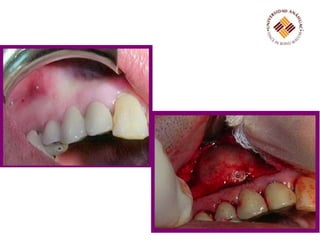

El proceso de odontogénesis o desarrollo dental pasa por varias etapas clave, incluyendo la yema dental, el casquete, la campana y el folículo dentario. Los quistes odontogénicos calcificantes son radiotransparentes y pueden mostrar calcificaciones irregulares dispersas, y se diagnostican diferencialmente de otros tumores dentales. El tratamiento incluye raspado quirúrgico o extirpación.